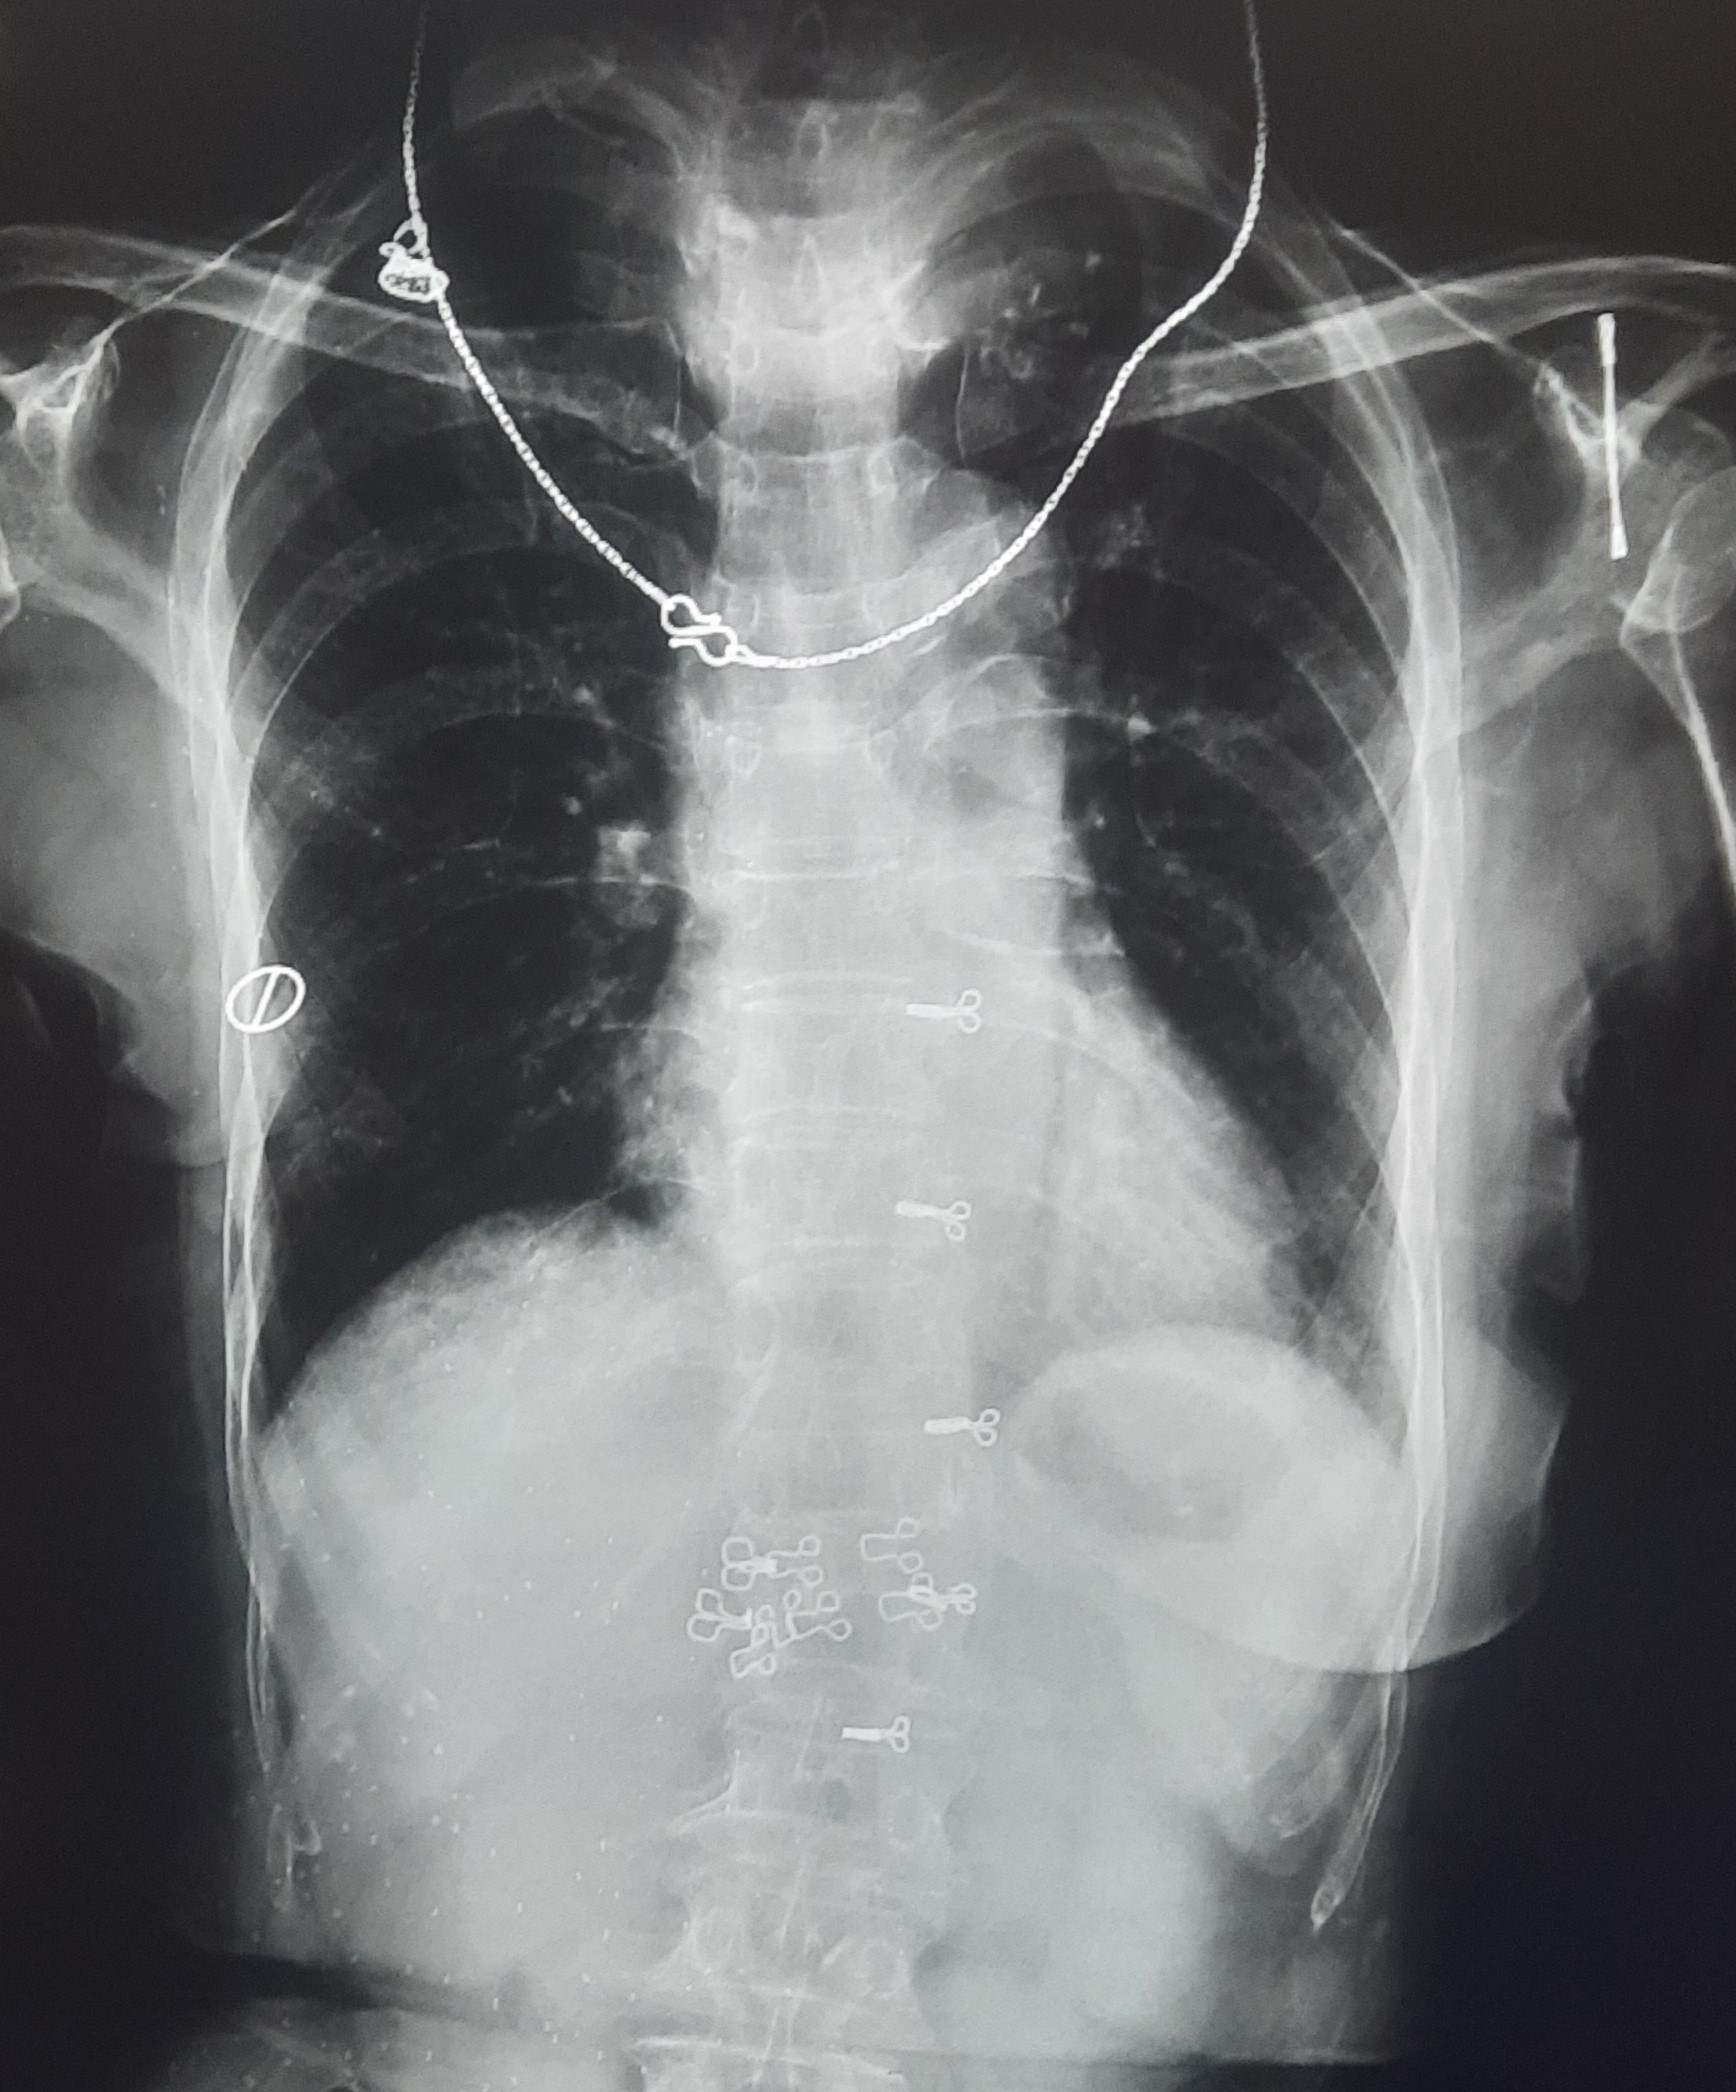

| 229 | IGGMC, Nagpur, Nagpur | P2 | 29-4243 | Faizal Khan | Consent taken on Paper | 28 Yrs. |

Provisional Diag : Disseminated TB Follow-Up

Final Diag : Disseminated TB (CxR- Right Sided Pneumothorax / TB Infiltration) |

TB Case (Confirmed) | Abnormality visible on x-ray |

View |